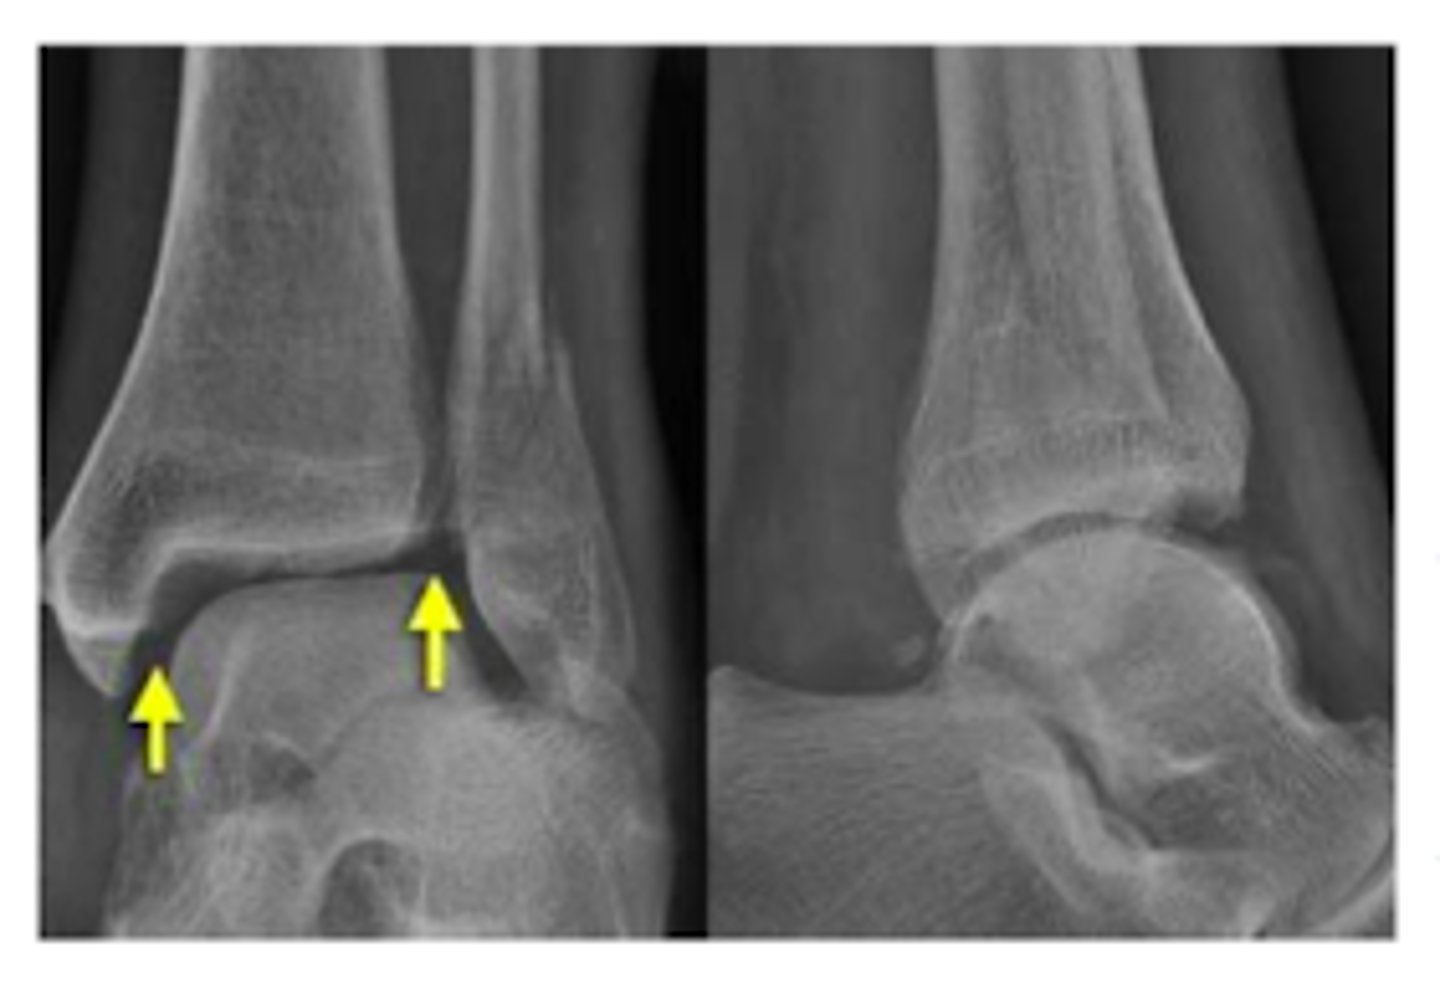

XR of Medial Malleolus Fx.

XR of Lateral Malleolus Fx with minimal displacement.